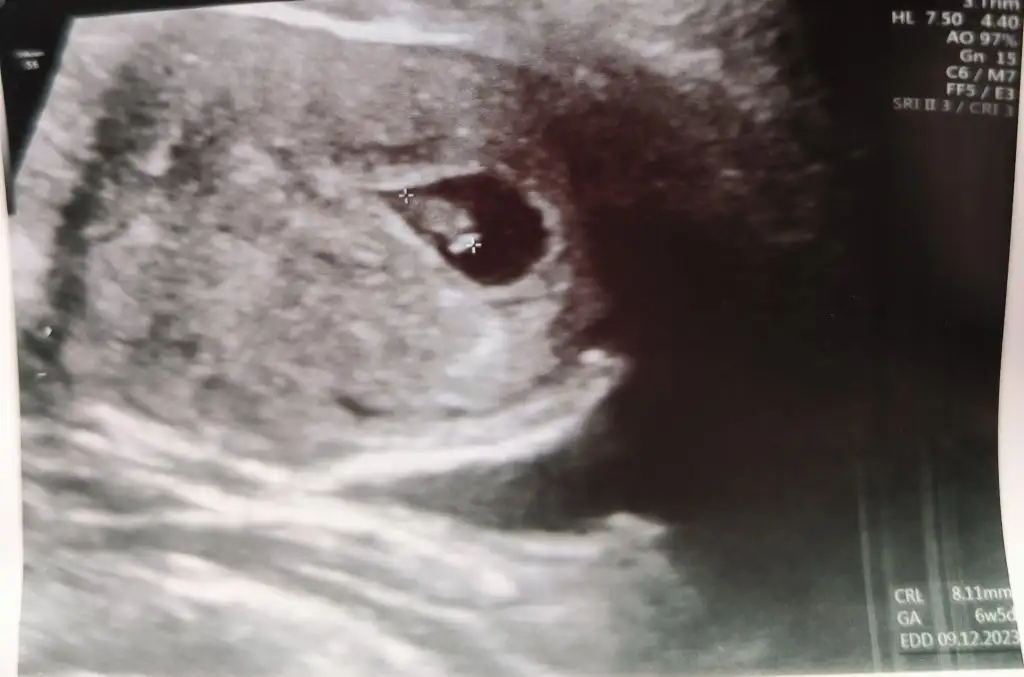

Ayy ben ultrasondan güzel anlarim ama bunu anlamadım valla totosu cozemedimİyi aksamlar kızlar Ankara'ya geldim sadece okuyup çıkıyorum bugün kontrolüm vardı herşey yolundaydı çok şükürbenim doktorum biraz çatlak ultrasona ne yazdı bakın

Ya normali bu benim eşim renkli görmek istediği için hoca 4 boyutlu açtı e bebiş de daha 7+4 olup çok küçük olunca doktor götü kafası diye yazarak anlatmaya çalıştı hahahah normal yani anlamaman. Diyorum ya bize anlatmasa ben de hayatta anlamazdimAyy ben ultrasondan güzel anlarim ama bunu anlamadım valla totosu cozemedim

Hay allahim yaa bende 12 haftalarda filan sandim renkli gorunceYa normali bu benim eşim renkli görmek istediği için hoca 4 boyutlu açtı e bebiş de daha 7+4 olup çok küçük olunca doktor götü kafası diye yazarak anlatmaya çalıştı hahahah normal yani anlamaman. Diyorum ya bize anlatmasa ben de hayatta anlamazdim